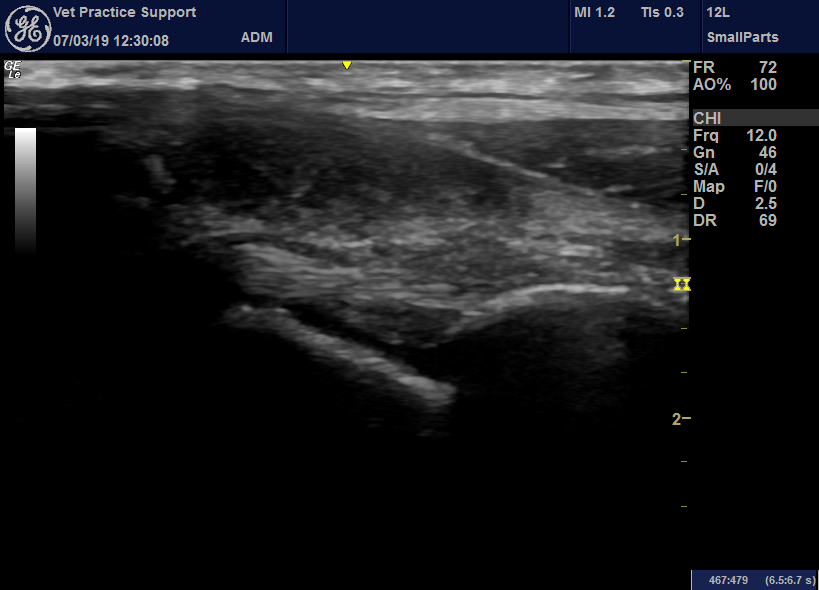

From www.vetpracticesupport.com

Sonographic features of septic arthritis in the dog Vet Practice Support Septic Arthritis Dog Vin 1,2 this is particularly true when recent surgery is. septic arthritis, degenerative arthropathies and immune mediated processes. septic arthritis manifests usually in only one joint. as the names suggest, in the infective group the inflammation is associated with a septic process and therefore this group of. Side effects that you should be aware of. nsaids are. Septic Arthritis Dog Vin.